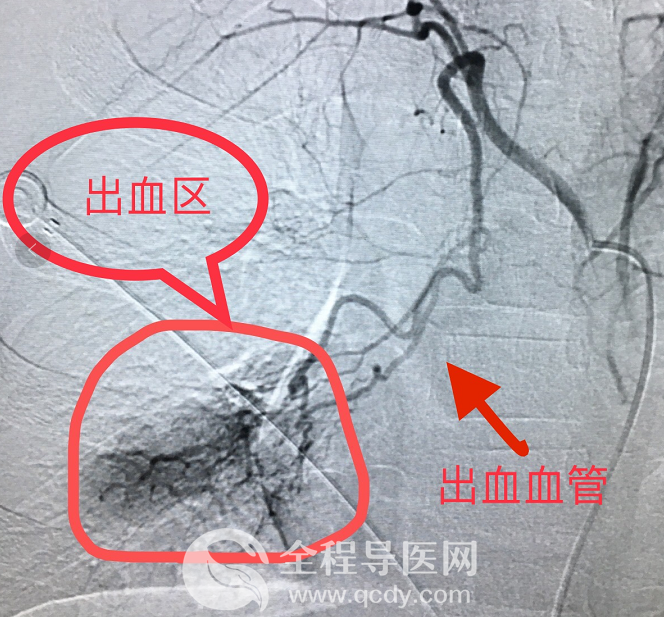

明確治療方案后,經(jīng)過與患兒家長詳細(xì)溝通并取得充分信任后,介入科李炯團(tuán)隊(duì)迅速完成手術(shù)相關(guān)準(zhǔn)備,患兒隨即被推進(jìn)介入手術(shù)室。手術(shù)過程中,患兒持續(xù)輸血、補(bǔ)液、呼吸機(jī)輔助呼吸等,李炯醫(yī)生通過嫻熟、精細(xì)的血管內(nèi)操作,精準(zhǔn)、快速尋找到血管出血點(diǎn),并注入明膠海綿顆粒以及PVA等栓塞劑,徹底對出血點(diǎn)進(jìn)行封堵。同時(shí)導(dǎo)管室護(hù)理團(tuán)隊(duì)密切配合,穩(wěn)定患兒生命體征,經(jīng)過近兩小時(shí)的緊張救治,患兒血色素逐漸上升。術(shù)后行造影證實(shí)出血點(diǎn)已經(jīng)確切止血。

情況危急,先行止血,爭取后續(xù)治療時(shí)間。取得患兒家長充分信任后,介入科團(tuán)隊(duì)快速做好術(shù)前準(zhǔn)備。李炯醫(yī)生在患兒的支氣管動(dòng)脈里面插入一個(gè)很細(xì)的管子,并注入PVA顆粒和明膠海綿顆粒進(jìn)行精準(zhǔn)栓塞,將出血點(diǎn)牢牢堵死,從而使血流不過去,手術(shù)歷經(jīng)2個(gè)小時(shí)。術(shù)后第二天,孩子恢復(fù)良好,并達(dá)到出院標(biāo)準(zhǔn)。